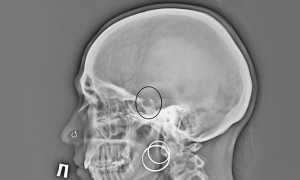

Пароксизмальная наджелудочковая аритмия на ЭКГ

Обратите внимание, что в обоих случаях единственной необходимой диагностикой является ЭКГ. Почему так? Именно на электрокардиограмме хорошо видны изменения в ритме.

Выше в статье мы уже упоминали о том, что диагностировать данное заболевание можно при помощи электрокардиограммы. На ней доктор четко увидит зубцы P, которых в нормальном состоянии быть не должно. Этого вполне хватит для того, чтобы поставить правильный диагноз. Поскольку изучив эти зубцы, жалобы пациента, врач сможет определить, о каком именно виде аритмии идет речь.